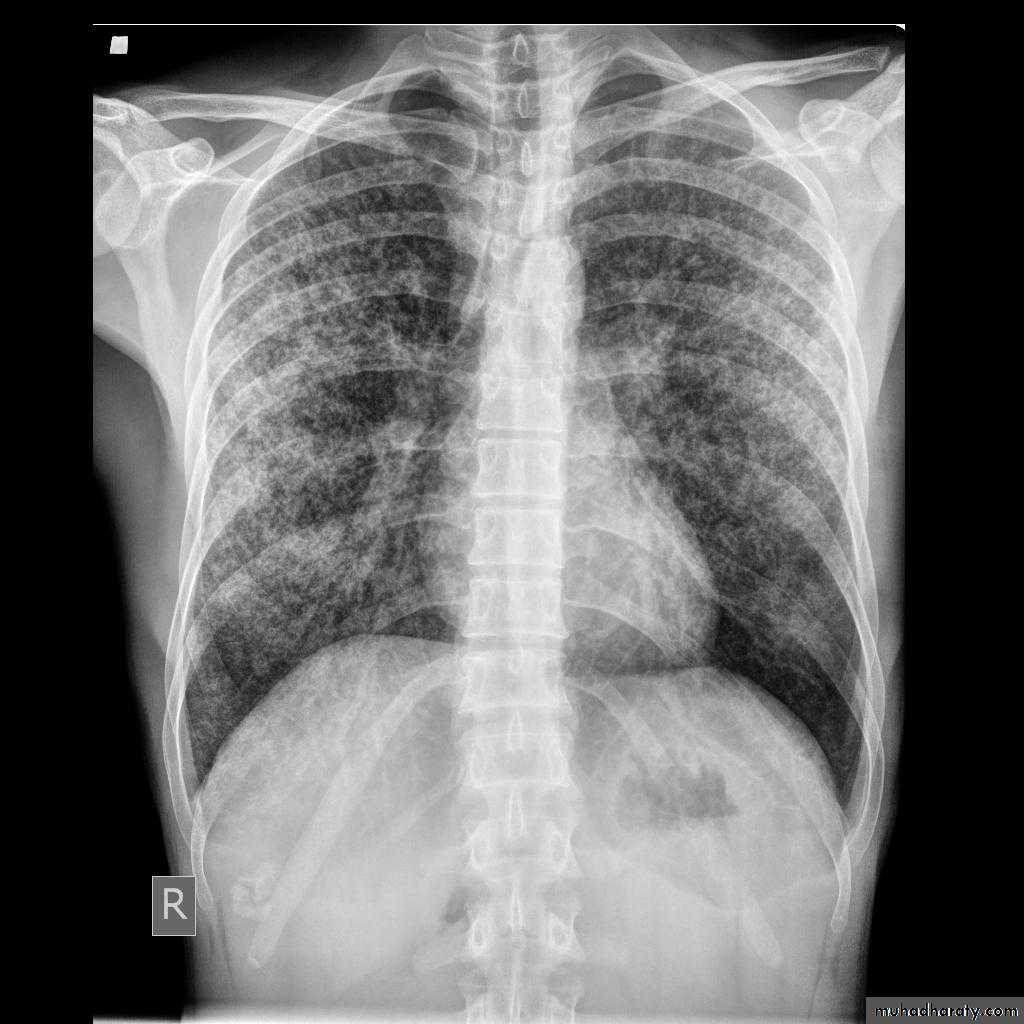

Metastisis to Lung (canon ball appearance)

CXR of adult, PA view shows Bilateral rounded radioopaque nodules of multiple sizes distributed all over both lung fields( Cannon ball appearance)